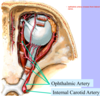

Draw the ciliary ganglion:

Label all: